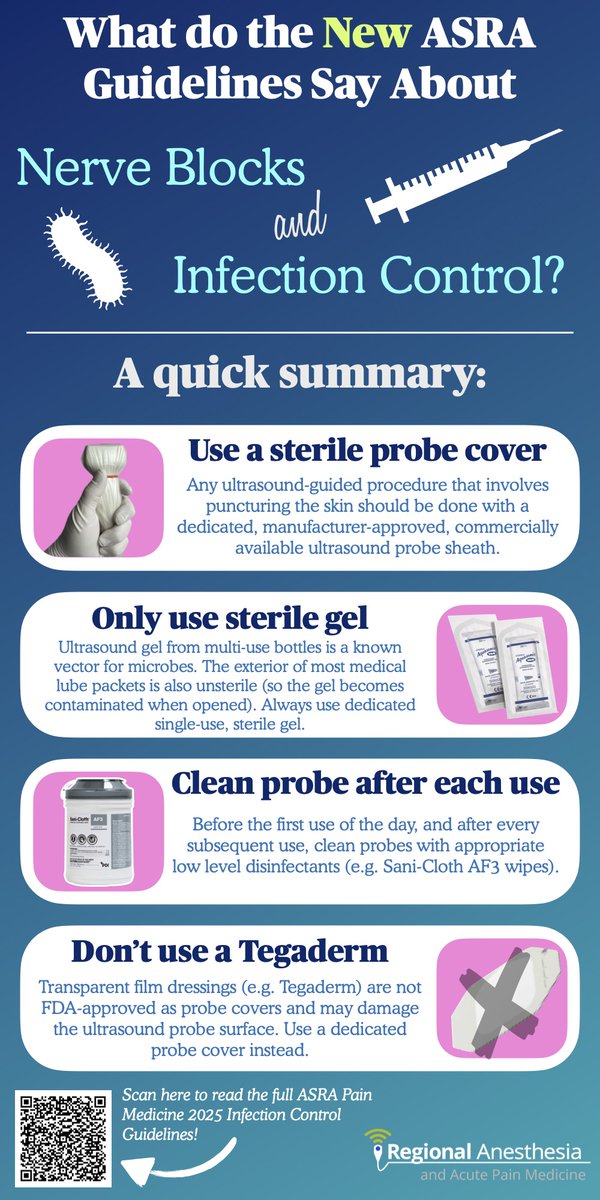

I sent this to my department today as a TL;DR version of the new ASRA Pain Medicine Guidelines on infection control. Feel free to use if it helps! There's a QR code to scan for the full article at the end...